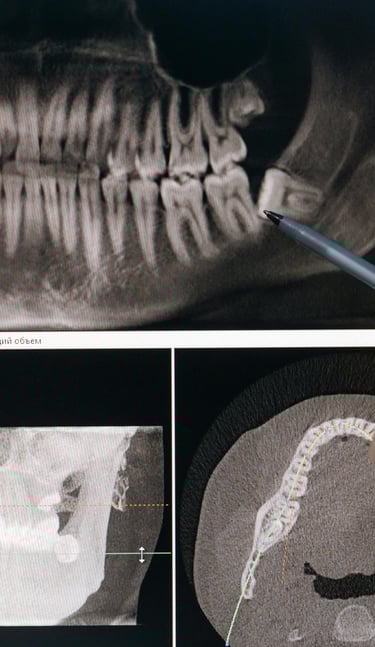

Je réaliserai tous les examens nécessaires (examen clinique, radiographies 2D et 3D, empreinte numérique, photographies…) afin d’établir un diagnostic précis

Je réaliserai tous les examens nécessaires (examen clinique, radiographies 2D et 3D) afin d’établir un diagnostic précis